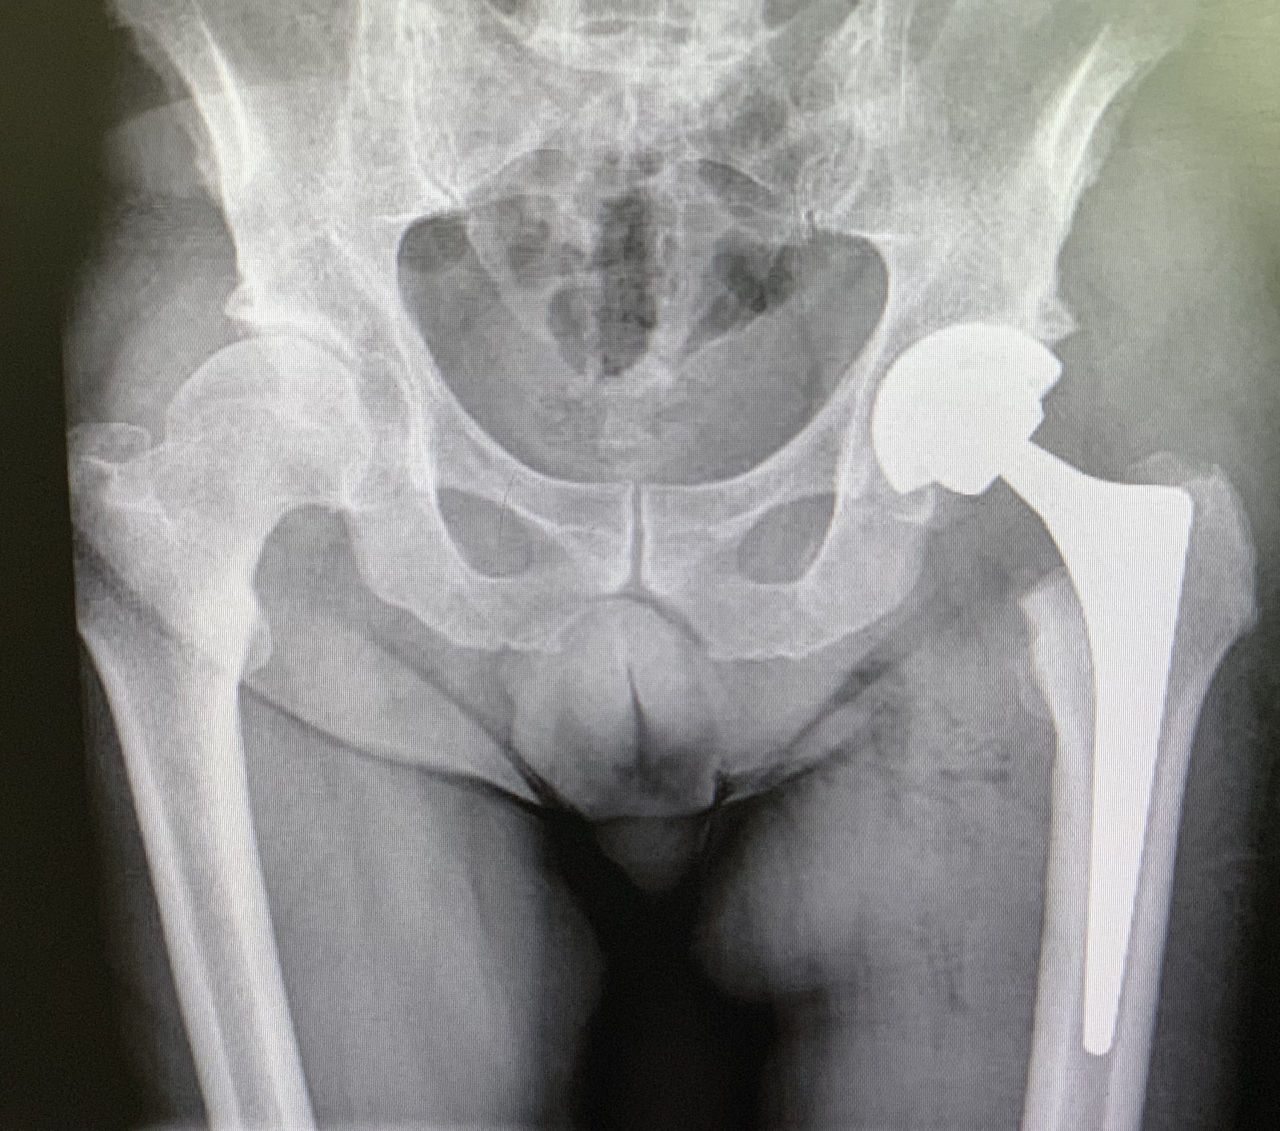

• Ortopedia dell'anca